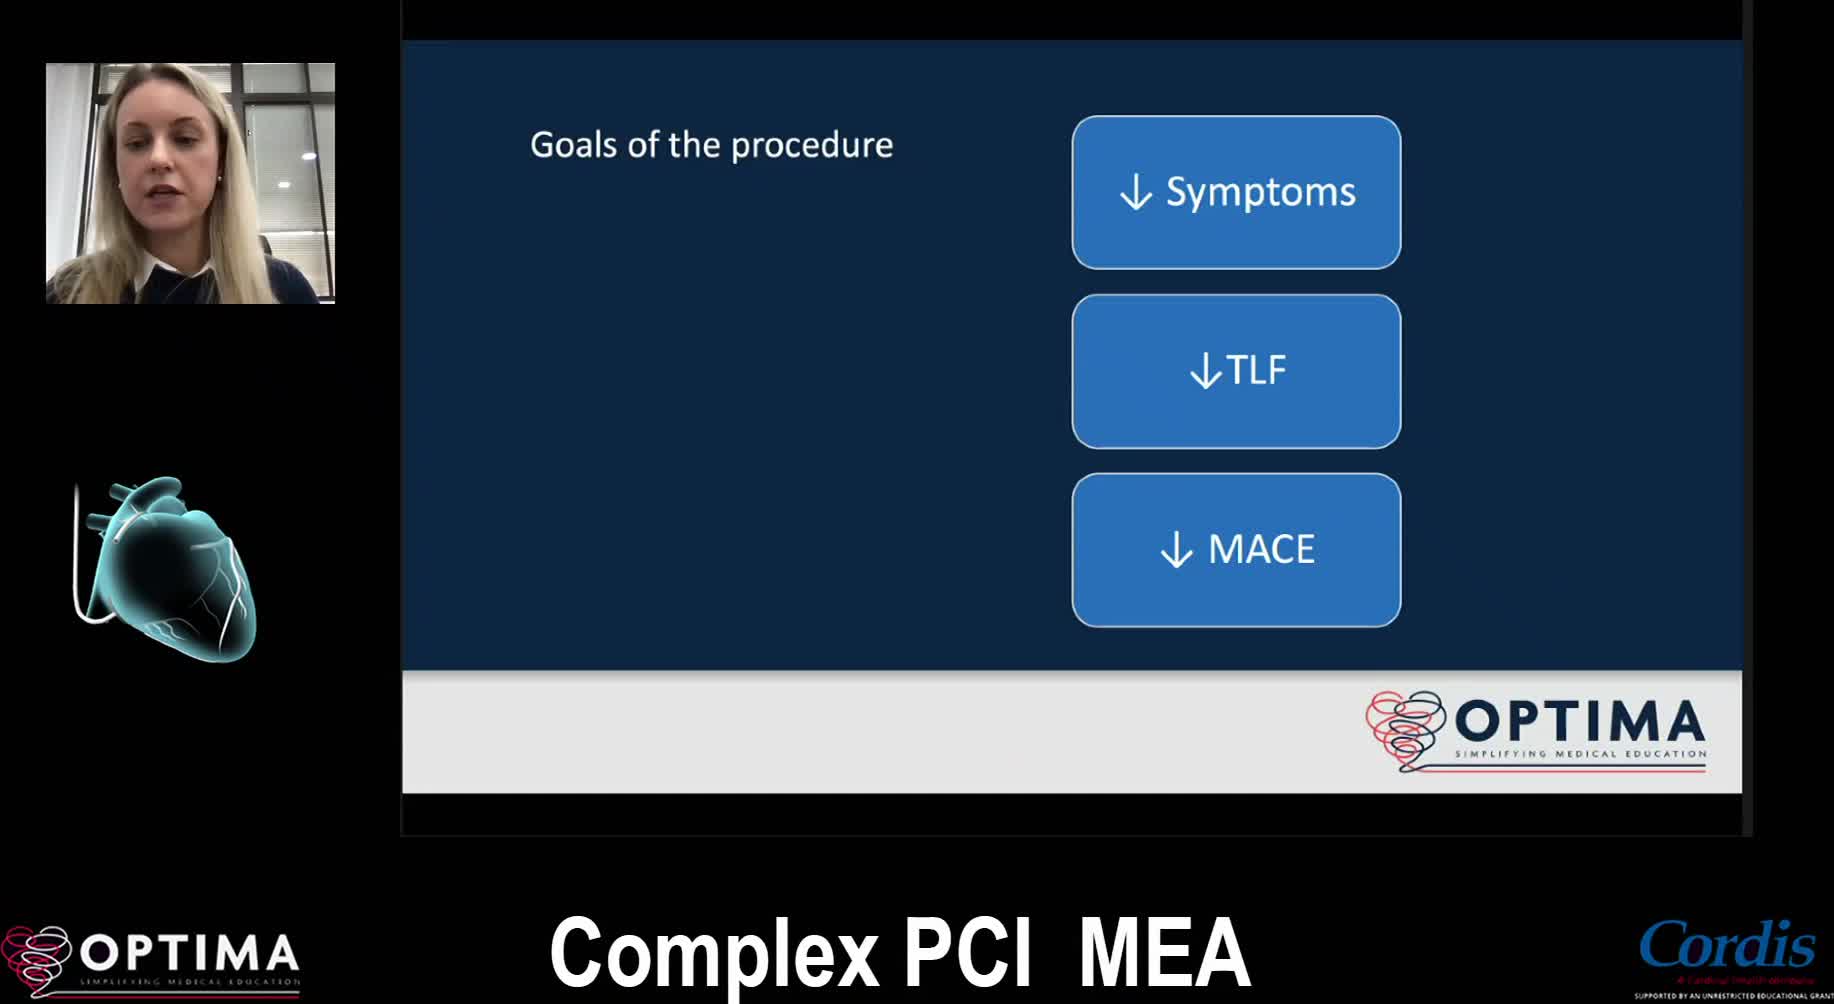

Complex PCI Middle East April 2021